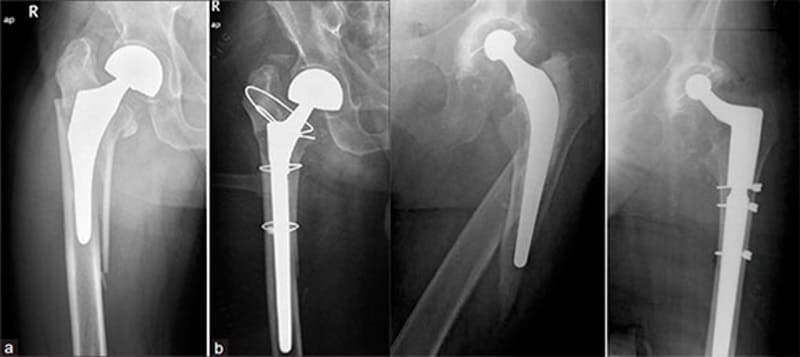

Результаты операций эндопротезирования тазобедренного сустава, выполненных сотрудниками Ортоцентра можно посмотреть здесь.